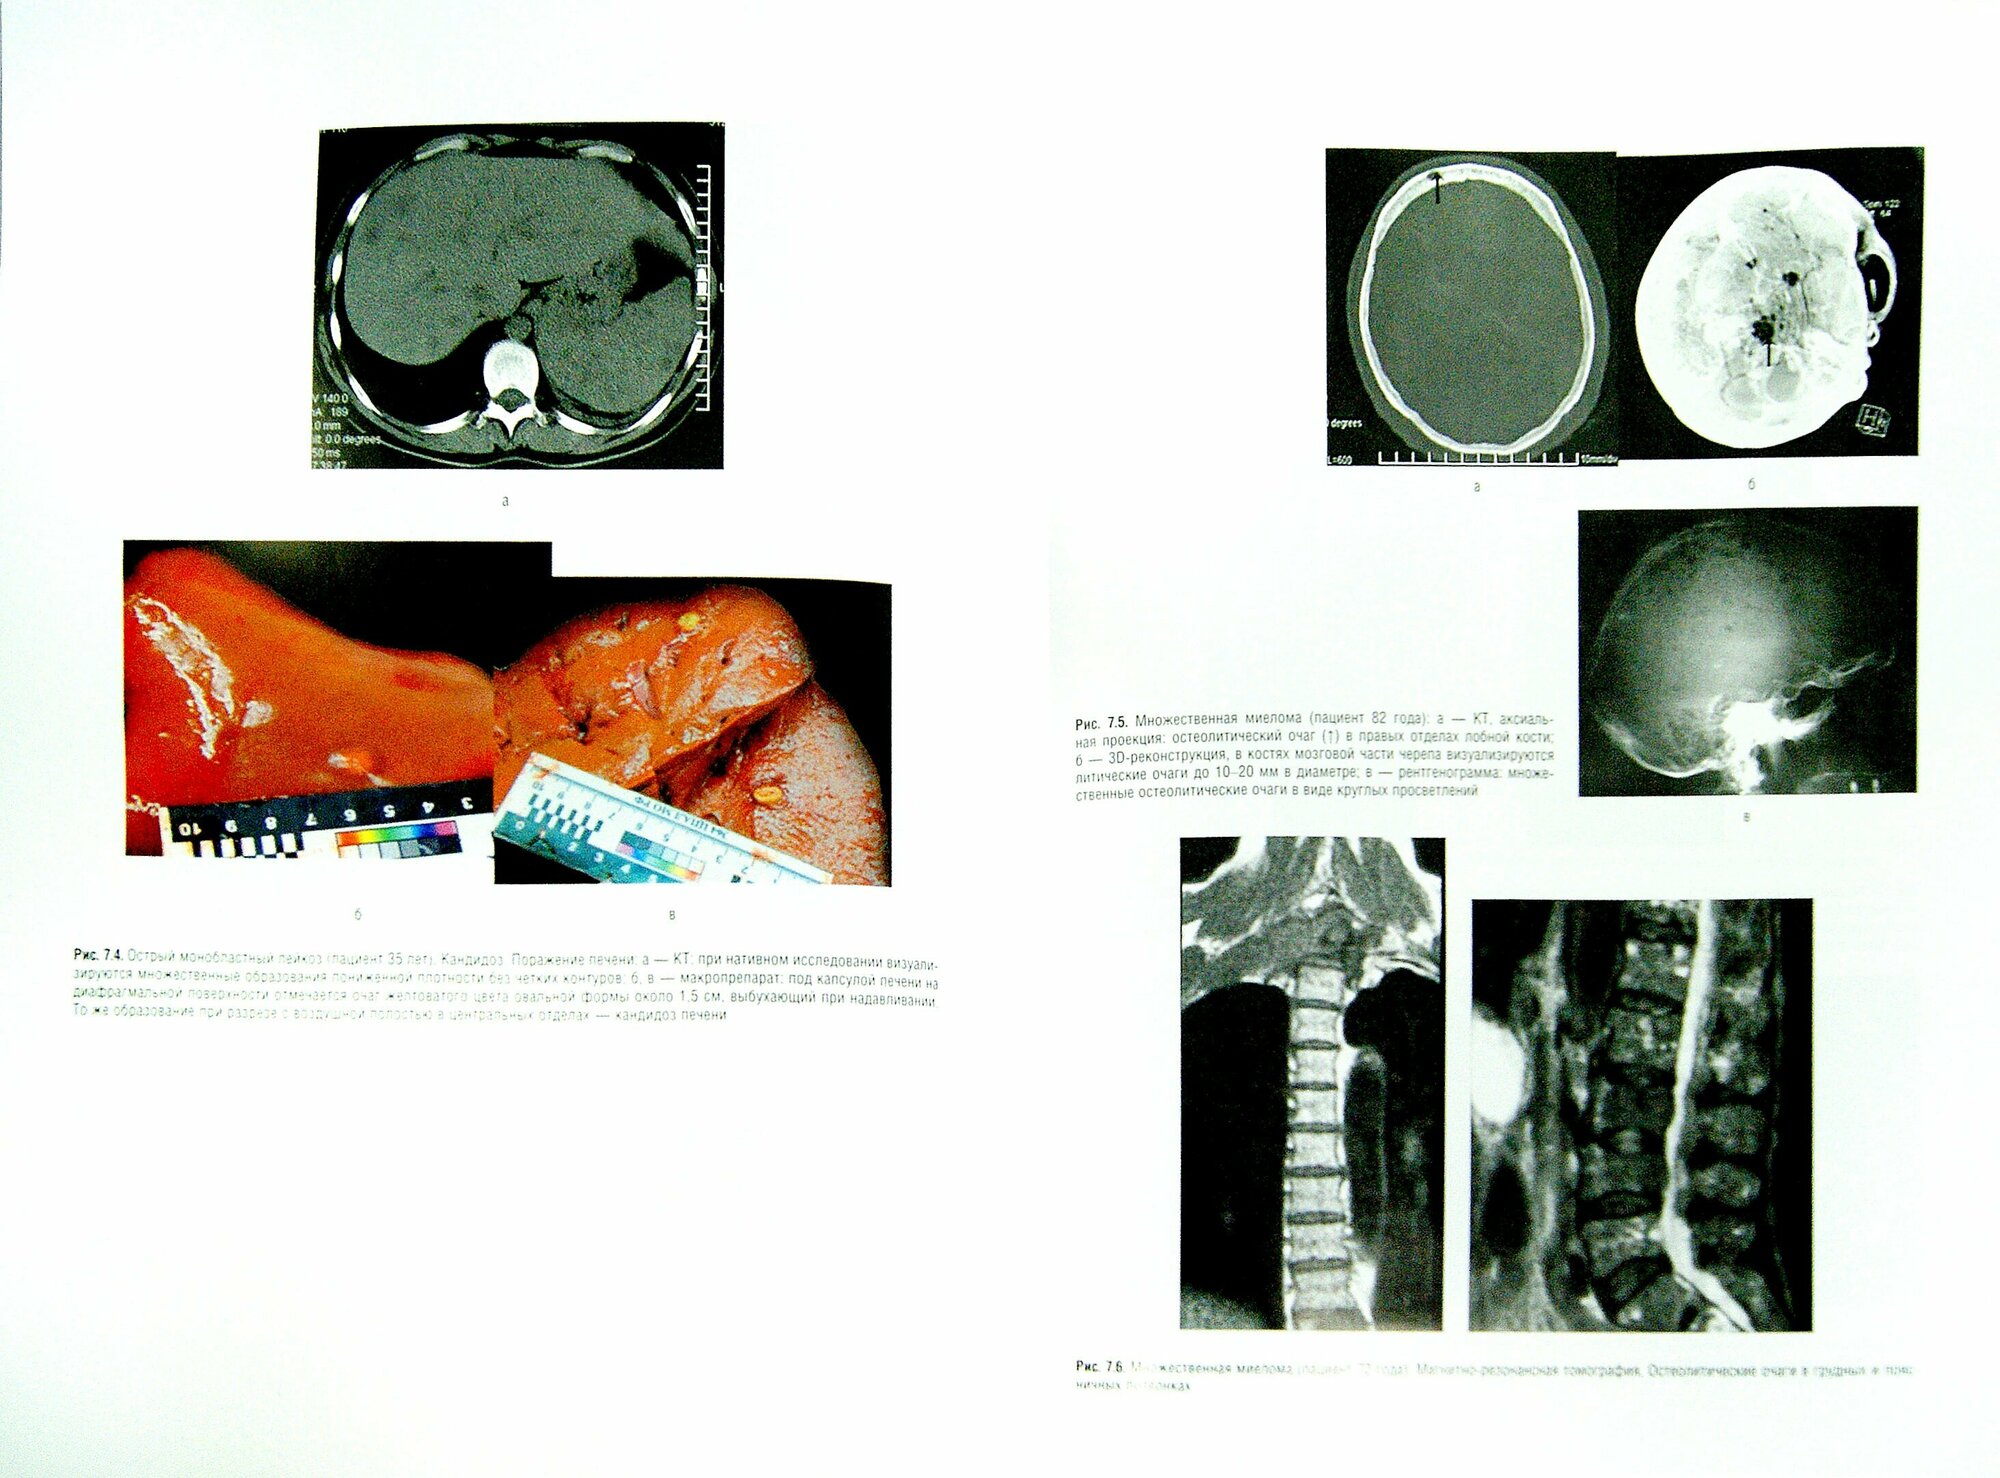

Книга Национальное руководство. Гематология / Рукавицын О.А. (Рукавицын Олег Анатольевич; Архипова Наталья Васильевна; Агеева Татьяна Августовна; Поп Василий Петрович), 2017

Национальное руководство по гематологии содержит всестороннюю информацию о диагностике и лечении болезней системы крови, направленную на облегчение трансляции неуклонно обновляющихся знаний в практическую деятельность врача. В книге проанализирован широкий спектр современных данных по этиологии, патогенезу, классификации, характеру клинического течения, эволюции и прогнозу злокачественных онкогематологических заболеваний. Даны основные представления об общих подходах к патологоанатомической и иммунологической диагностике. Освещены проблемы гемостаза, анемий, тромбоцитопений, а также заболеваний, обусловленных нарушением регуляции системы комплемента. По всем нозологическим формам на основе результатов доказательной медицины разработаны актуальные алгоритмы лечения и отдельно указаны подробные схемы лекарственной терапии и показания к лучевой терапии. Изложены принципы трансплантации гемопоэтических стволовых клеток и переливания компонентов крови. Тщательно рассмотрены критерии оценки ответа на терапию с учетом международных стандартов. Приведены особенности гематологии детского возраста. Большое внимание уделено проблемам и перспективам организации гематологической помощи в России, а также вопросам гематологического образования. Дополнительно отражены наиболее важные осложнения и последствия (включая отдаленные) противоопухолевой терапии, неотложные состояния, ведение болевого синдрома, тошноты и рвоты, а также парентеральное питание в гематологической практике. Обсуждены также особенности амбулаторного ведения больных и сведения о роли и возможностях интегративной медицины в гематологии. Издание предназначено врачам-гематологам, онкологам, терапевтам, интернам, клиническим ординаторам и аспирантам медицинских вузов.